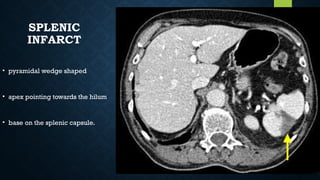

INFARCT

• pyramidal wedge shaped

• apex pointing towards the hilum

• base on the splenic capsule.

SPLENIC INFARCT • pyramidal wedgeshaped • apex pointing towards the hilum • base on the splenic capsule.